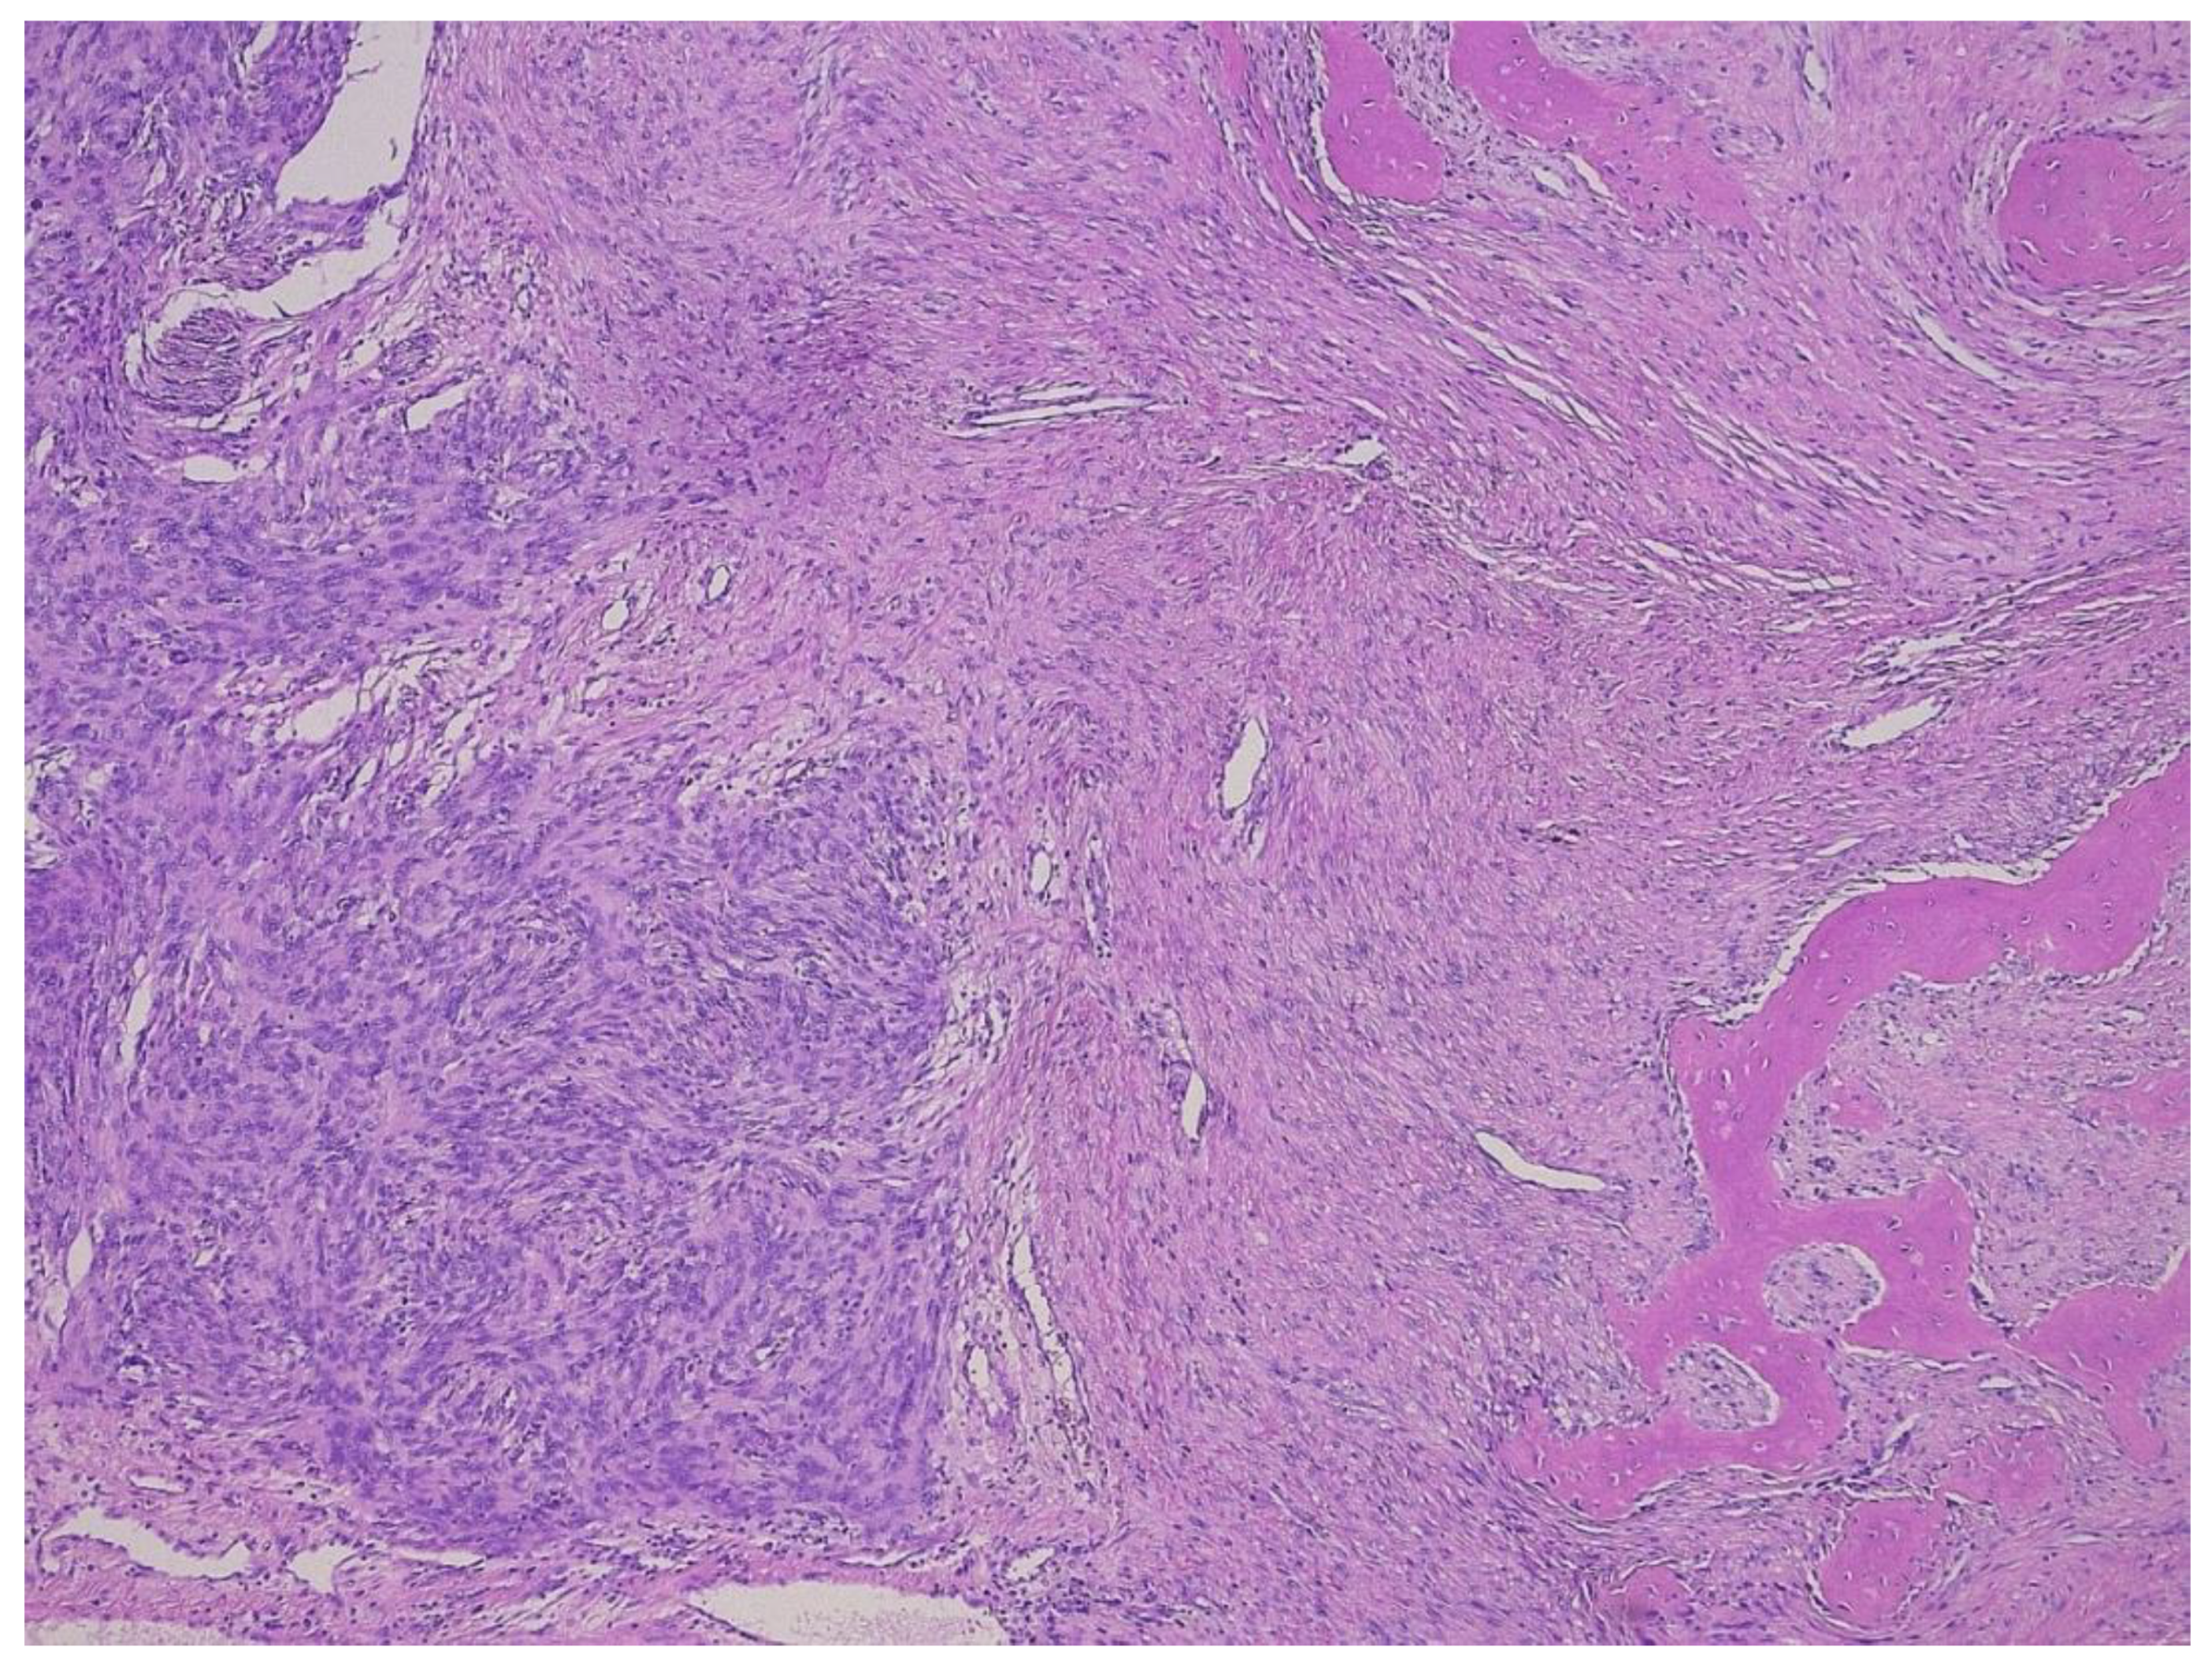

3. Dedifferentiated Liposarcoma

- Thway, K.; Jones, R.L.; Noujaim, J.; Zaidi, S.; Miah, A.B.; Fisher, C. Dedifferentiated Liposarcoma: Updates on Morphology, Genetics and Therapeutic Strategies. Adv. Anat. Pathol. 2016, 23, 30–40. [Google Scholar] [CrossRef]

- Dei Tos, A.P.; Marino-Enriquez, A.; Pedeutour, F. Dedifferentiated liposarcoma. In WHO Classification of Tumours Editorial Board. Soft Tissue and Bone Tumors; International Agency for Research on Cancer: Lyon, France, 2020; pp. 39–41. [Google Scholar]

- Thway, K.; Robertson, D.; Thway, Y.; Fisher, C. Dedifferentiated Liposarcoma With Meningothelial-like Whorls, Metaplastic Bone Formation, and CDK4, MDM2, and p16 Expression: A Morphologic and Immunohistochemical Study. Am. J. Surg. Pathol. 2011, 35, 356–363. [Google Scholar] [CrossRef]

- Le Guellec, S.; Chibon, F.; Ouali, M.; Perot, G.; Decouvelaere, A.-V.; Robin, Y.-M.; Larousserie, F.; Terrier, P.; Coindre, J.-M.; Neuville, A. Are Peripheral Purely Undifferentiated Pleomorphic Sarcomas with MDM2 Amplification Dedifferentiated Liposarcomas? Am. J. Surg. Pathol. 2014, 38, 293–304. [Google Scholar] [CrossRef]